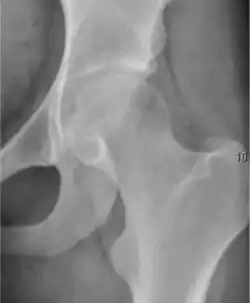

Plain radiography allows us to categorize the hip as normal or dysplastic or with impingement signs (pincer, cam, or a combination of both). Besides these, pathologic processes like osteoarthritis, inflammatory diseases, infection, or tumors can also be identified (Figure 1).[1]

Figure 1.

-

Radiography in normal hip -

X-ray in pincer impingement type of hip dysplasia -

X-ray of cam -

Hip in osteoarthritis -

Septic arthritis